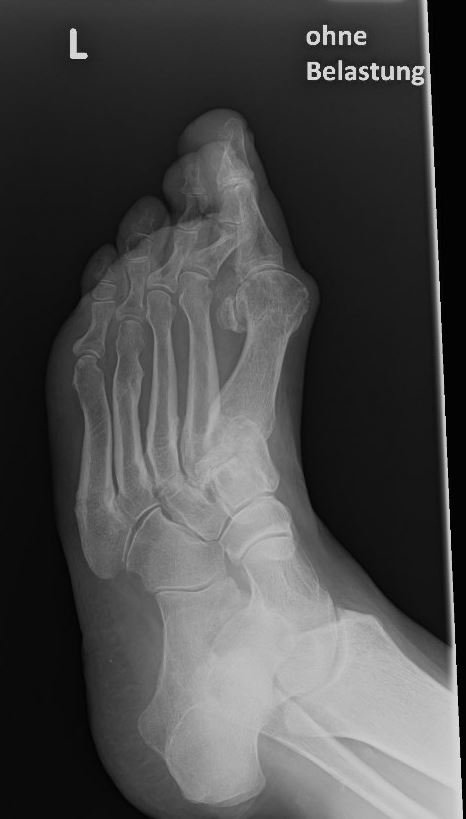

Eine Röntgenaufnahme unter Belastung mit Abbildungen des ganzen Fußes a. p. (mit 15-20° Röhrenkippung) und seitlich, sowie Schrägaufnahmen, reichen meist zur Diagnose. Manchmal ist ein MRT und DVT ergänzend hilfreich. Selten wird die Indikation für ein SPECT CT gestellt (Abb. 6).

Zum Lesen der Bildbeschreibung und zur Vollansicht bitte das Bild anklicken. Bild: C. Hase.

• konventionelle Röntgenbilder mit Belastung im Stehen a. p. und seitlich, ggf. schräg (Abb. 9, 10 und 11).